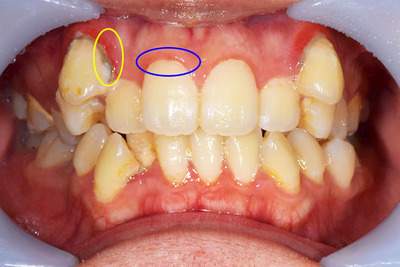

AFTER

歯周病症例の治療後

黄色:歯の周りに付着していた黒い歯石がなくなっています。

青色:歯石を除去することでは周囲の歯ぐきの色がピンク色になっているのがわかります。これは炎症がおさまったことを意味します。

年齢・性別 30代・女性

主訴 歯のクリーニングをしたい

治療内容 歯石除去(スケーリング、再評価)

治療費 約2,000円(保険治療内)

治療期間 2週間(歯石を除去して、歯肉の回復を待つのに2週間待機します)

リスク・副作用 歯石除去後は歯ぐきがひきしまるため、歯が伸びたような感じになることがあります。

また、歯が冷たいものにしみやすくなることもあります。